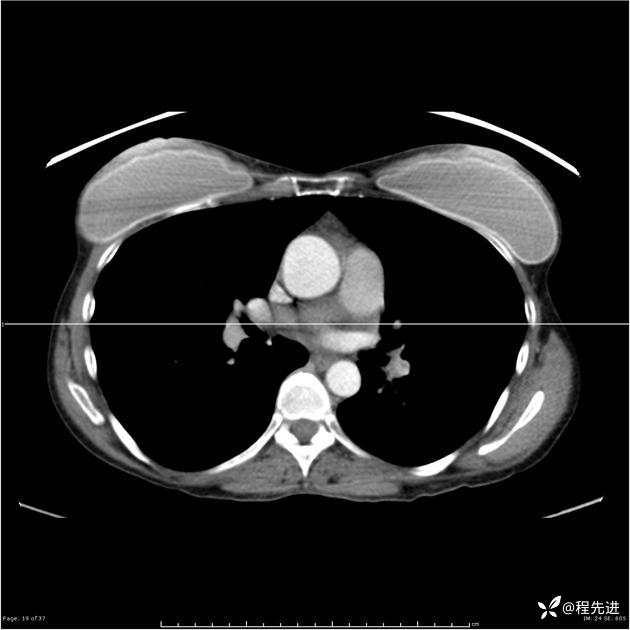

病例女,53岁,气管、左主支气管、下叶支气管内结节,乳头状瘤?期待你的精彩解读

女,53岁

乳头状瘤?